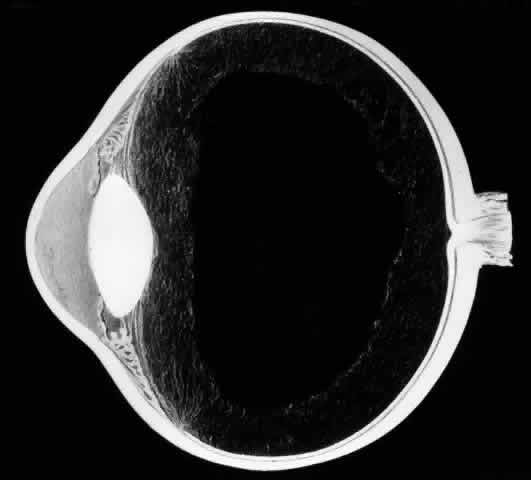

Biomicroscopic Findings Preceding Development of a Giant Tear

The earliest biomicroscopic changes preceding the development of a giant retinal tear were syneresis and liquefaction of the vitreous gel, converting the posterior and central portions of the vitreous body into a large lacuna (Fig. 14). Later, the anterior gel became condensed, and its posterior aspect formed an equatorially oriented membrane extending across the vitreous cavity (Fig. 15). This membrane did not oscillate with ocular movements, suggesting that it was under tension. Marked contraction of this membrane seems responsible for tearing the retina along the posterior border of the vitreous base (Fig. 16). Liquefied vitreous gel facilitated inversion of the posterior retinal flap (Fig. 17).

Fig. 14. The earliest biomicroscopic change in the vitreous prior to the development of a nontraumatic giant retinal break is liquefaction of the vitreous gel, which converts the central portion of the vitreous gel into a large lacuna.

Fig. 15. In later biomicroscopic changes preceding a nontraumatic giant retinal break, the anterior vitreous gel becomes condensed and a membrane forms its posterior aspect.

Fig. 16. Contraction of this equatorially oriented membrane extending across the vitreous cavity produces a giant tear along the posterior border of the vitreous base.